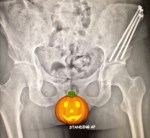

The x-rays looked good and the screws were still intact. Dr. Santore asked that I start weaning off some of the medications that I was on as he thought I was maybe oversedated. I was on lower dosages of narcotics then I’d been on in the past and the concoction of meds was the same mix I’d been on before too. I was able to stop the muscle relaxer with success and to lower my nerve pain medication. Then I just started weaning my narcotic as much as I could tolerate. Although, the feelings I had stuck around even once I was off all meds and that’s why we now think I had BP fluctuations.